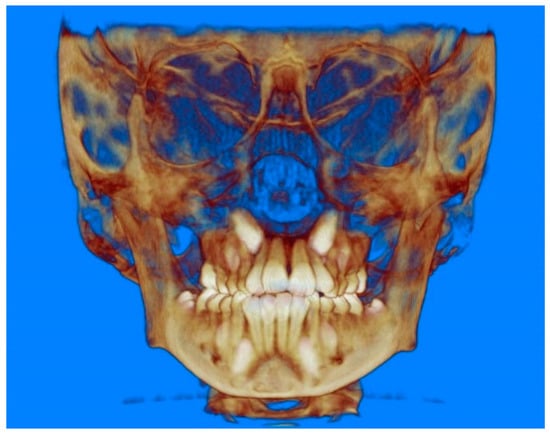

- Evaluation of impacted teeth, a common indication of CBCT in orthodontics. The advantages of CBCT include assessment of the tooth location and position, the stage of development, and status of adjacent teeth. CBCT is justified in these cases, because CBCT has the capability of evaluating the impacted teeth and adjacent structures more accurately than 2D conventional imaging. The benefit–risk ratio is favorable, especially if the CBCT volume is collimated to the impacted tooth. Figure 1, Figure 2, Figure 3 and Figure 4 show an example of impacted maxillary canines, and their proximity to the maxillary lateral incisors. Figure 1 shows an intraoral photograph. The benefit of CBCT acquisition in this case includes the ability to visualize the canines and the lateral incisors in three dimensions, which can be visualized in Figure 2 and Figure 3. In this case, the maxillary right lateral incisor exhibited external root resorption, a finding that would be difficult to see on a conventional 2D panoramic radiograph. Figure 4 shows a Maximum Intensity Projection of a panoramic view derived from the CBCT volume. This unique view is free of magnification, distortion, ghost images, and overlaps frequently seen in conventional 2D panoramic radiography.